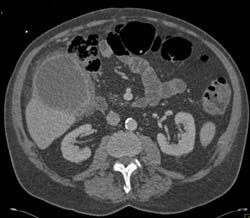

Stent in Common Bile Duct (CBD) in Patient With Cholangiocarcinoma With IVC Clot